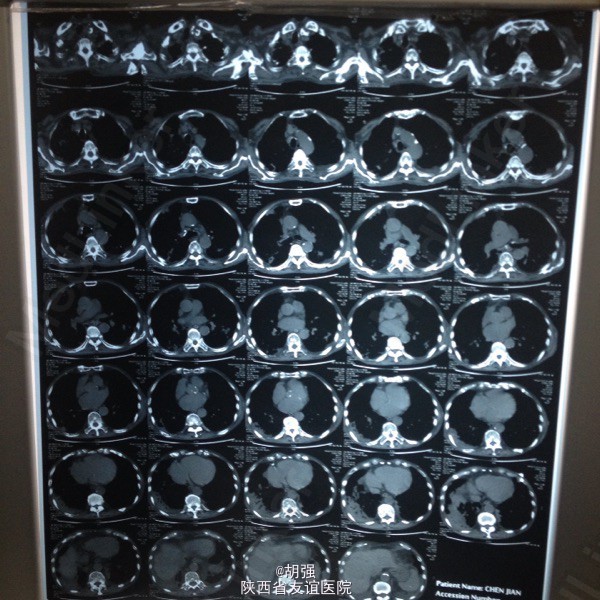

老年男性患者七十六岁。 主诉:反复咳嗽、咳痰10年,加重2月。 现病史:患者10年前受凉后出现咳嗽、咳痰,于当地医院给抗感染治疗后症状消失。此后每遇劳累或者季节交替时,反复出现咳嗽、咳痰、胸闷、气短,且逐年加重,多次住院,行胸部CT、肺功能、血气分析等相关检查,诊断为:慢性阻塞性肺疾病急性加重期,给于抗感染、平喘治疗后均能缓解(具体用药及剂量不详)。2月前受凉后,咳嗽、咳痰、气短症状加重,咳大量白色黏痰,于外院抗感染对症治疗效果不佳,遂来我院。 既往有甲状腺功能亢进病史8年,继发心房纤颤,行I131治疗;有腔隙性脑梗死病史5年。

查体:口唇略紫绀,口腔黏膜无充血、糜烂、溃疡;颈静脉怒张,桶状胸,两侧呼吸动度及语颤减弱,叩诊呈过清音,两肺呼吸音粗糙,可闻及哮鸣音及湿性啰音。心率110次/分,律不齐,心音强弱不等,各瓣膜听诊区未闻及病理性杂音。腹平软,无压痛,肝脾肋下未及,双下肢水肿。 血常规: 白细胞14.01XE9/L、中性细胞比率91%、血红蛋白170g/L、血小板370X10E9/L。

慢性阻塞性肺疾病急性加重期,肺结核?肺真菌病?支气管扩张?慢性肺源性心脏病,心功能IV级,甲状腺功能亢进症,I131治疗后,心房纤颤,脑梗死。 外院给予特治星及氟康唑治疗效果不佳。入院后给予舒普深3.0静注2次/日联合莫西沙星片o.4口服1次/日,多索茶碱0.2十甲泼尼龙20mg2次/日,镁极化液250ml十异舒吉20mg静点,酚妥拉明10mg静点及强心、利尿治疗后好转。

复查血常规正常,血气分析提示:低氧血症,代射性碱中毒,电解质示:钾低。考虑:代谢性碱中毒由低钾所致。